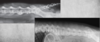

16

identify anomaly

Butterfly anomaly which is very specific to bulldog breeds (most have at least one if not more).

Vertebra is abnormally shaped like a butterfly.

Abnormality of ossification centers.

Two triangular units.

VD/DV views can catch it

Mostly asymptomatic.